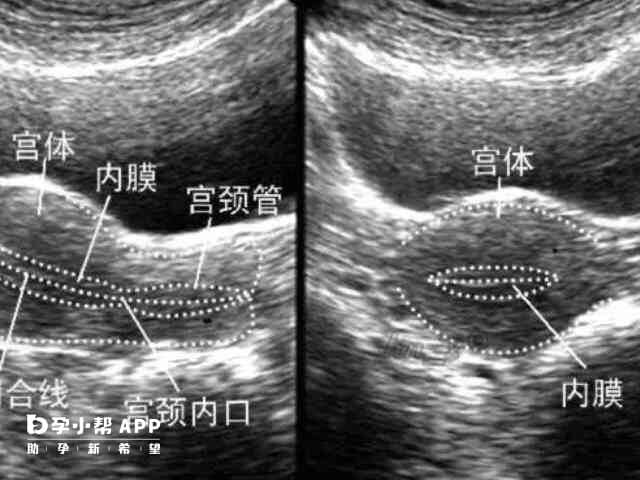

子宫内膜生理周期厚度变化详解,排卵期最厚可达12mm!

通常女性的子宫内膜会在性激素的调节下,产生周期性的厚度变化,拥有正常的子宫内膜是成功受孕的前提条件。从子宫内膜厚度变化图中可以看出,内膜厚度变化主要有三个阶段,分别是增殖期、分泌期和月经期。一般月经后子宫内膜处于增殖期且较薄,而在月经前,也就是排卵期在激素刺激下,子宫内膜可达到10mm左右,有利于受精卵着床。女性子宫内膜厚度变化图解析子宫内膜厚度变化图表一般来说,女性子宫内膜厚度会随体内激素和生理...